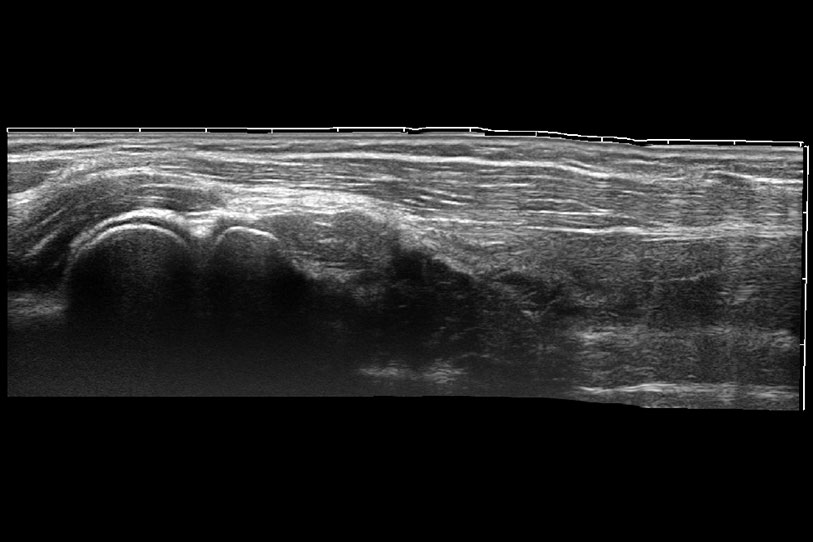

ProPet 70 進(jìn)一步提升了微米成像算法,更加注重對(duì)基礎(chǔ)原始圖像的還原和保留,在有效減少斑點(diǎn)噪聲、增強(qiáng)組織邊界顯示的同時(shí),避免過(guò)度優(yōu)化丟失真實(shí)的解剖信息。

為精細(xì)結(jié)構(gòu)及組織邊緣提供高清晰度的圖像和更大的成像視野。幫助減輕醫(yī)生的用眼疲勞,快速精準(zhǔn)獲得測(cè)量的數(shù)據(jù)。